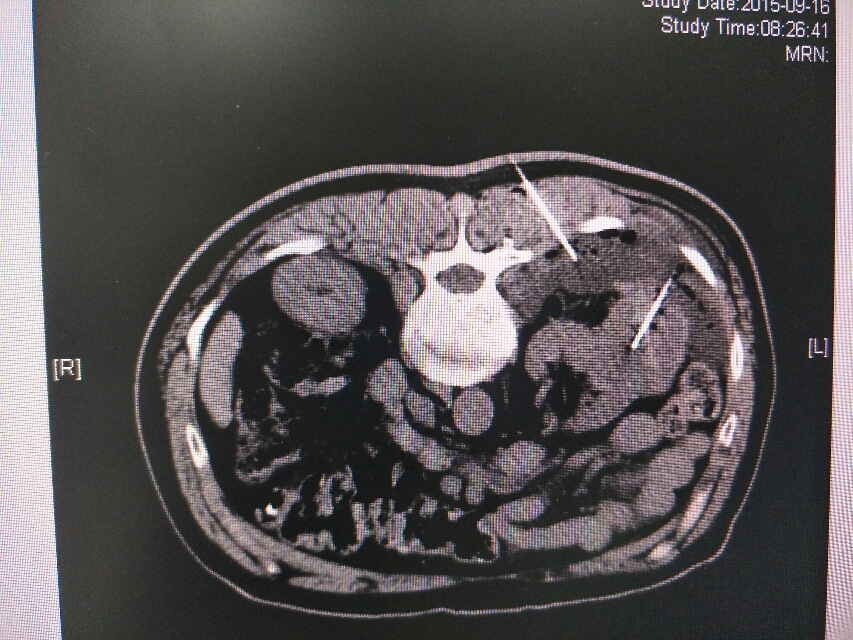

肾癌化疗及靶向治疗效果差,后予射频消融手术